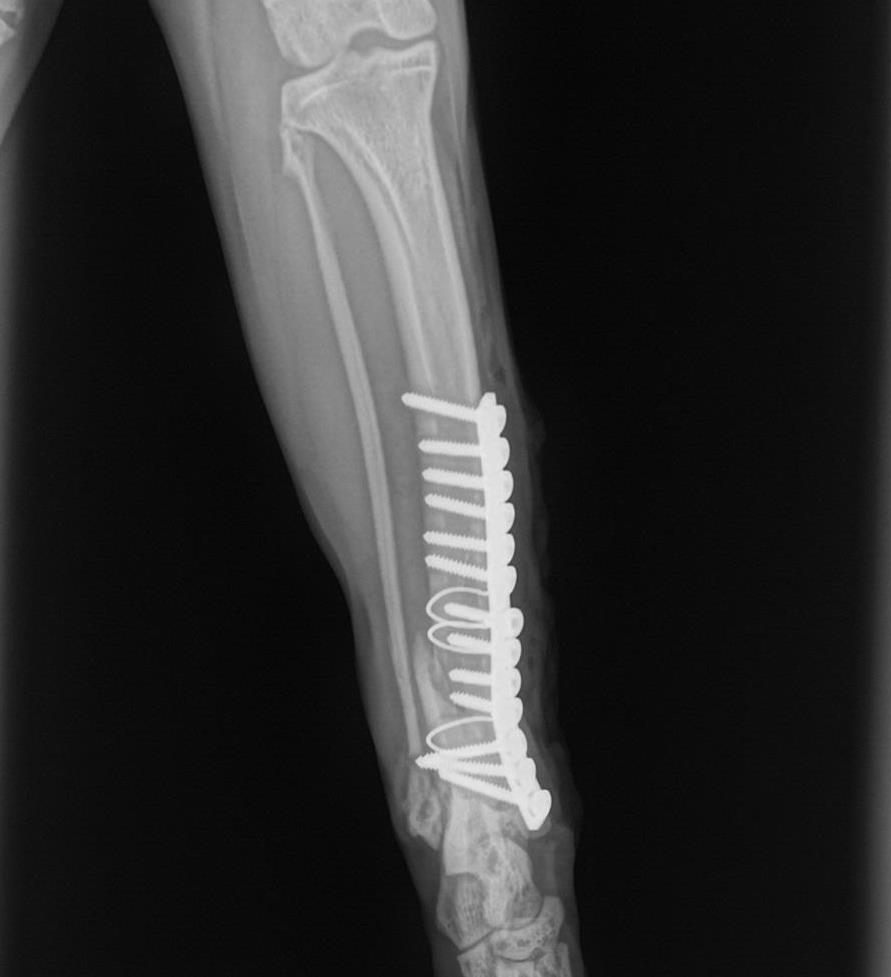

I repaired the bone with a stainless steel plate, thirteen screws, and two wires. Then I reinforced the repair with a splint.

![]() Here you can see the plate, screws, and wires used to repair the shattered bone. |

![]() To fix the shattered tibia, I used thirteen screws, a plate, and two wires. |